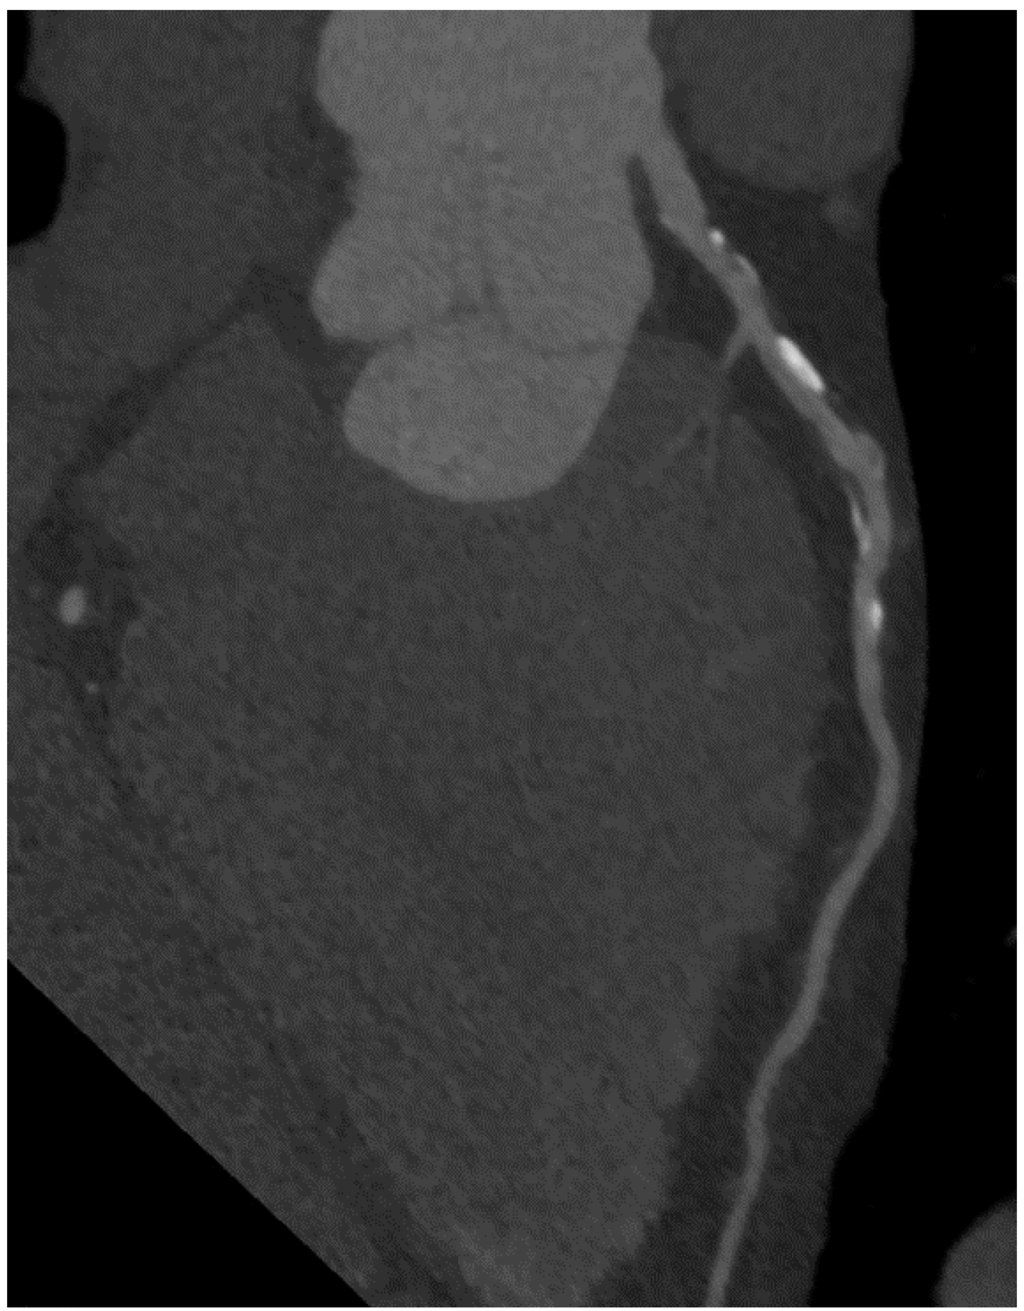

5. Coronary CT Angiography

6. Imaging of Coronary Plaques and Stenoses